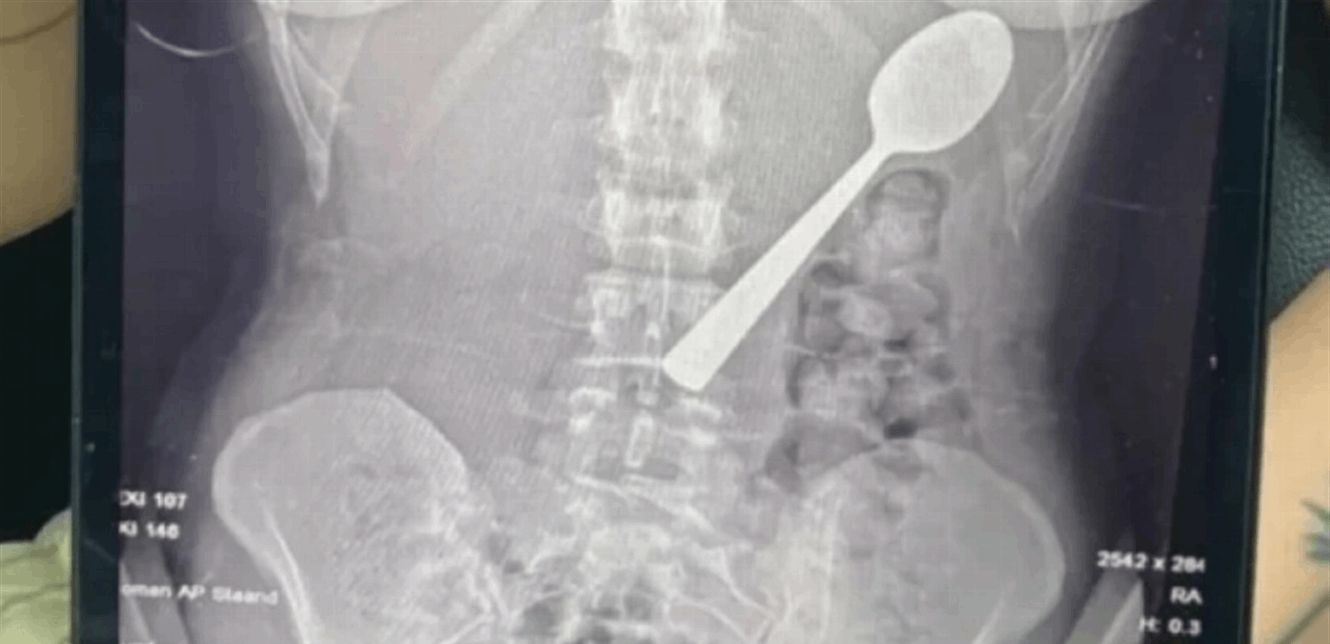

وعند مراجعة الأطباء، تبيّن أن الملعقة أكبر من أن تمر عبر الجهاز الهضمي بشكل طبيعي، ما استدعى تدخلاً عاجلاً. وبعد انتظار يومين تحت المراقبة، خضعت ريمي لعملية منظار معدة تحت التخدير الموضعي، حيث قام الأطباء بتدوير الملعقة بحذر داخل المعدة لسحبها، ما تسبب بنزيف طفيف والتهاب مؤقت في الحلق.

وأكد الفريق الطبي عدم تسجيل مضاعفات دائمة، فيما قررت ريمي الاحتفاظ بالملعقة بعد استخراجها كـ"ذكرى" للحادثة، مشيرة إلى أن شريكها يخطط لتحويلها إلى قطعة فنية داخل المنزل.